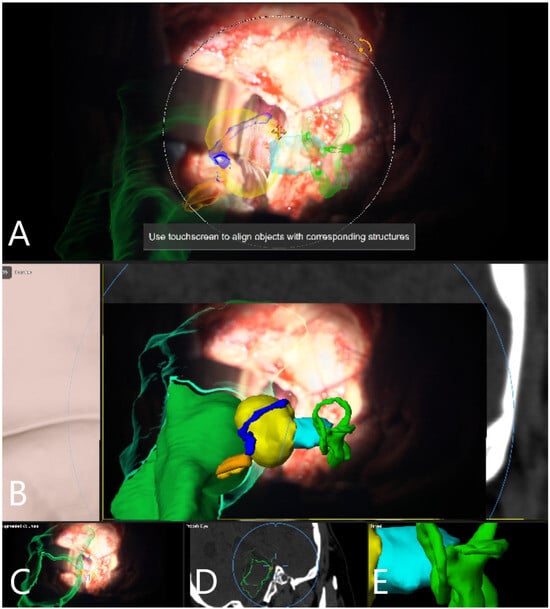

| Patient Number | Segmented Structures in AR Advantages: Craniotomy Planning, Dural Opening, Relations of Tumor to CN V, Localization of Origin of CVI and CVIII at the Brain Stem, Relations of Tumor to Brain Stem, Localization of IV Ventricle, Segmentation of Tumor Cyst, Localization of Structures of the Middle Ear for Facilitation of Drilling on Inner Acoustic Meatus, Relations of Tumor to Arterial Vessels and to Petrosal Vein | ||||||||||

|---|---|---|---|---|---|---|---|---|---|---|---|

| Sigmoid Sinus | Transverse Sinus | Tumor Outline | CN VII and VII Origin at Brain Stem | CN V | Petrous Vein | Arterial Vessels (AICA, PICA, SCA) | Brain Stem | Middle Ear, Cochlea and Semicircular Canals | Pyramidal Tract | IV Ventricle | |

| 28 | + | + | + | − | − | − | + | − | − | − | − |

| 29 | + | + | + | − | − | + | + | − | − | − | − |

| 30 | + | + | + | − | − | + | + | + | − | + | − |

| 31 | + | + | + | − | − | + | − | + | + | − | − |

| 32 | + | + | + | − | − | − | − | + | + | − | + |

| 33 | + | + | + | + | − | − | − | + | − | − | + |

| 34 | + | + | + | + | − | − | − | + | + | − | − |

| 35 | + | + | + | + | − | − | − | + | + | . | − |

| 36 | + | + | + | + | + | − | − | + | − | − | − |

| 37 | + | + | + | − | − | + | − | + | + | − | − |

| 38 | + | + | + | + | + | + | − | + | + | − | − |

| 39 | + | + | + | − | + | − | − | + | + | − | − |

| 40 | + | + | + | + | + | − | − | + | + | − | − |

| 41 | + | + | + | − | + | − | − | + | + | − | − |

| 42 | + | + | + | + | + | − | − | − | − | − | |

| 43 | + | + | + | + | + | + | − | + | + | − | − |